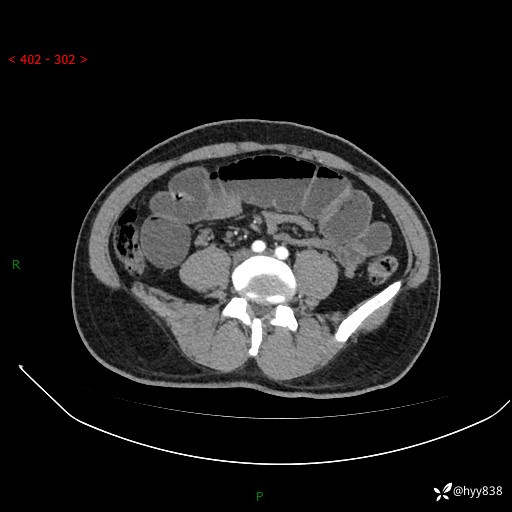

年轻男性,腹痛5月余。除了肠梗阻,你还能看到什么---结果公布~

主诉:腹痛5月余。

现病史:患者于5月前无明显诱因开始出现腹痛,上明显,为间断性胀痛不适,无畏寒发热,无心慌气促等特殊不适,遂来我院。我院门诊遂以“腹痛原因待查”收入我科。 起病以来,患者精神、饮食、睡眠欠佳,大小便正常。体力体重无明显变化。

腹部CT增强扫描(动脉期+静脉期)